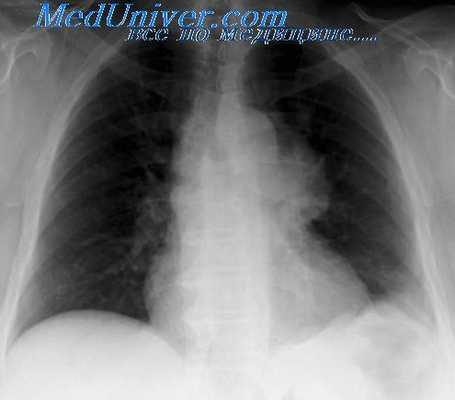

Дермоидные кисты и тератомы имеют довольно специфическую рентгенологическую картину. К числу наиболее характерных рентгенологических признаков относится локализация дермоидных кист и тератом. Известно, что последние, как правило, располагаются в переднем средостении.

Но в отличие от многих других локализующихся здесь опухолей дермоидные кисты и тератомы обычно располагаются непосредственно за грудиной в ретро-стернальном пространстве и чаще всего в средней трети длинника средостения (у 15 из 21 больного G. И. Волкова, у 8 из 12 наших больных). Редко отмечается локализация в нижнем отделе средостения или на всем его протяжении при больших размерах дермоида.

По отношению к средней линии патологическая тень в 80—90% случаев (Дезев и Дюмон) имеет одностороннее расположение: по одним авторам — чаще справа (Б. Г. Стучинский, Дезев и Дюмон), по другим — чаще слева (наблюдения С. И. Волкова и наши). Редко дермоиды располагаются срединно (в 4,2% случаев, по Б. Г. Стучинскому). При этом они могут выходить за оба контура срединной тени.

В большинстве случаев тень дермоидов имеет овальную форму с косо расположенным длинником по отношению к длиннику срединной тени, реже неправильно округлую форму. При росте дермоидной кисты в междолевую щель длинник ее овала принимает горизонтальное положение (А. Е. Прозоров). Размеры патологической тени могут колебаться в широких пределах — от небольших до громадных. В последнем случае бывает затемнена почти вся половина грудной клетки.